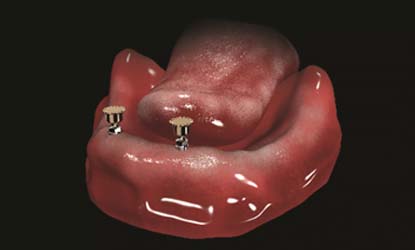

Problema: Trūksta visų dantų

Tikslas:

Pakeisti trūkstamus dantis išimamais protezais (ekonomiškiausias gydymo būdas)

Rezultatas:

Atkurta kramtymo ir estetinė funkcija išimamais dantų protezais